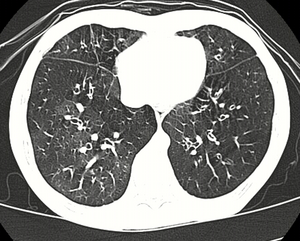

| High resolution CT scan showing bronchiolitis obliterans with mosaic attentuation, bronchiectasis, air trapping and bronchial thickening[3] | |

Medical imaging

Early in the disease chest radiography is typically normal but may show hyperinflation.[6] As the disease progresses a reticular pattern with thickening of airway walls may be present.[4][6] HRCT can also show air trapping when the person being scanned breathes out completely; it can also show thickening in the airway and haziness in the lungs.[11] A common finding on HRCT is patchy areas of decreased lung density, signifying reduced vascular caliber and air trapping.[6] This pattern is often described as a "mosaic pattern", and may indicate obliterative bronchiolitis.[6]